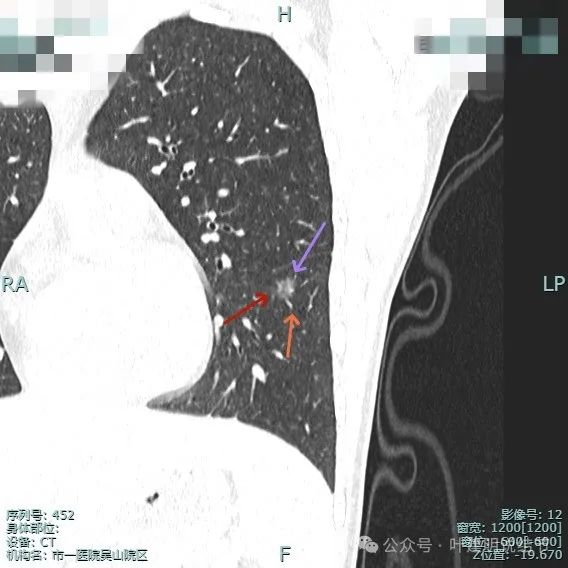

再看主要病灶的靶重建情况:

左侧病灶10:

病灶表面不平有分叶与凹凸,密度也不均匀,有点状实性成分,邻近胸膜(叶间裂)。

表面有毛刺,灶内有小空泡征,边缘毛糙不平,密度显得不均匀。

部分边缘有毛刺或小棘突,病灶边上有扩张的细支气管,整体内部密度欠均匀。

边缘毛糙,血管进入,灶内密度显得杂乱。

有扭曲的血管进入血管,表面有凹陷与分叶。

密度不太纯,表面不平,血管有异常增粗。

胸膜有轻微牵拉,表面不平,多处微小血管进入,整体密度显得不匀。

血管征明显、灶内小空泡征、胸膜牵拉、边缘细毛刺征。

整体看上去密度不均、边缘不平、灶内空泡征以及细毛刺征均明显。